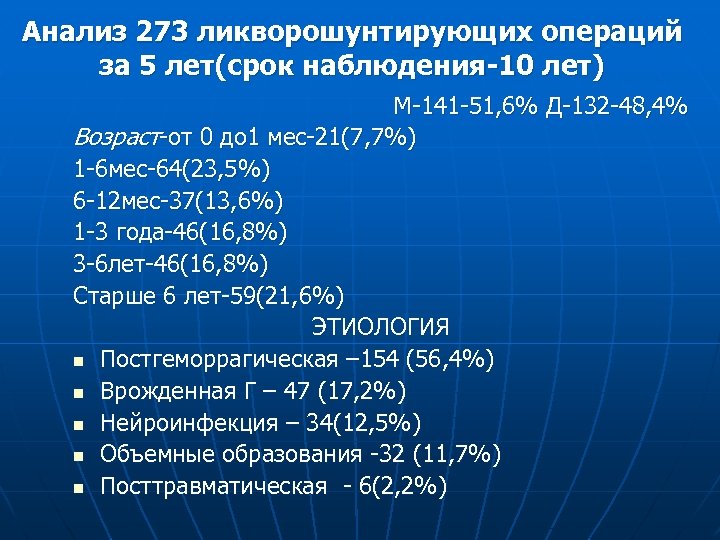

Анализ 273 ликворошунтирующих операций за 5 лет(срок наблюдения-10 лет) М-141 -51, 6% Д-132 -48, 4% Возраст-от 0 до 1 мес-21(7, 7%) 1 -6 мес-64(23, 5%) 6 -12 мес-37(13, 6%) 1 -3 года-46(16, 8%) 3 -6 лет-46(16, 8%) Старше 6 лет-59(21, 6%) ЭТИОЛОГИЯ n Постгеморрагическая – 154 (56, 4%) n Врожденная Г – 47 (17, 2%) n Нейроинфекция – 34(12, 5%) n Объемные образования -32 (11, 7%) n Посттравматическая - 6(2, 2%)